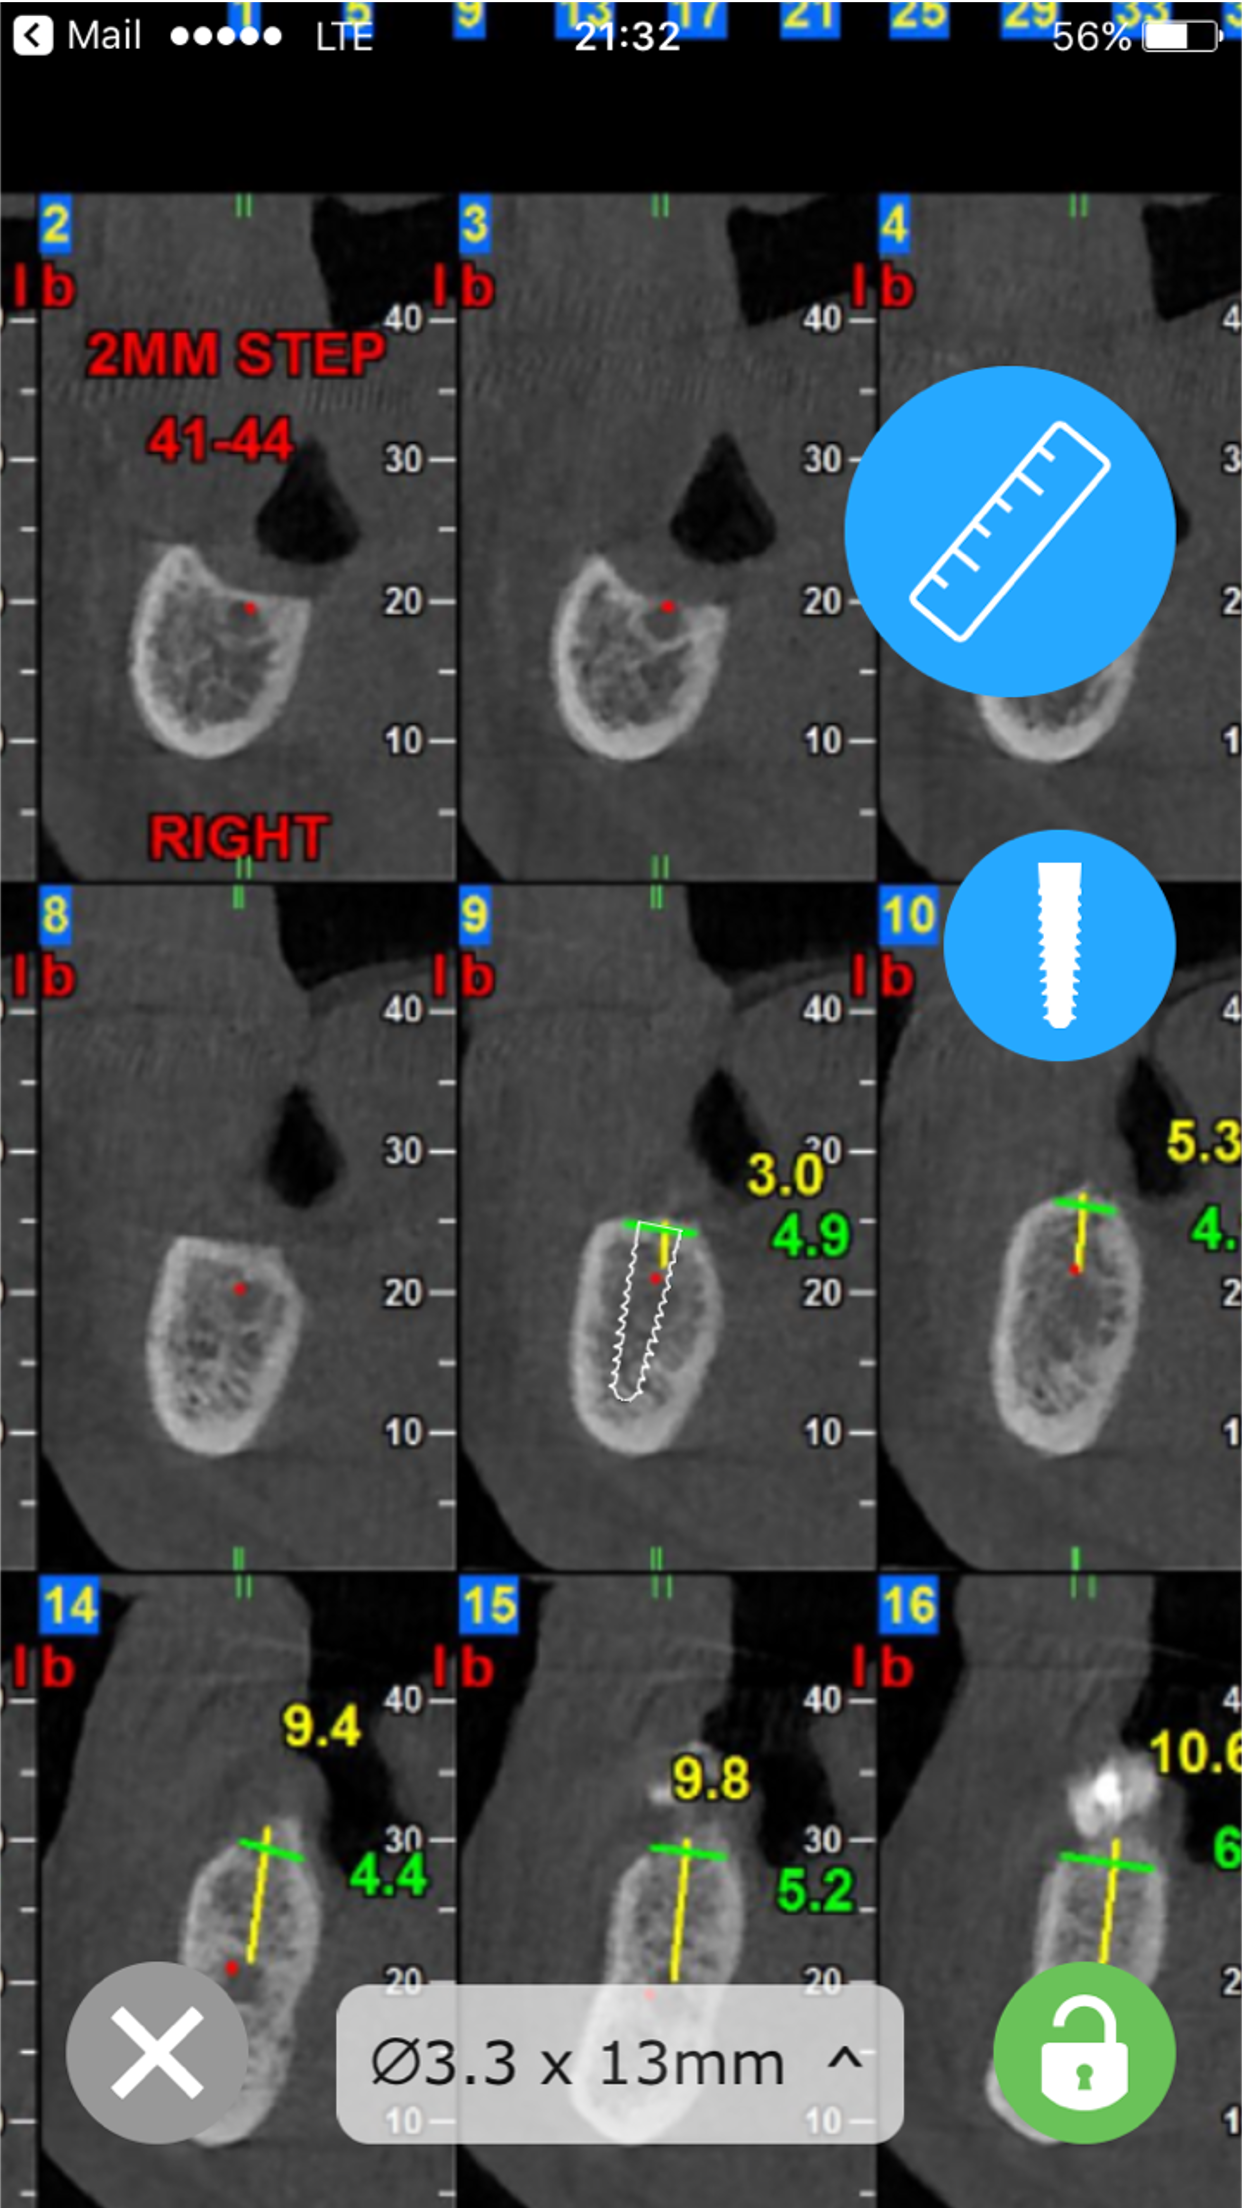

CBCT-Ruler was developed by Maxillofacial surgeon, to make the process of pre-surgical planning easy and mobile. The app opens a CBCT PDF file send by Dental imaging center and helps the practitioner easily measure distances. Another feature for the implant specialist, allows to introduce an implant to the CBCT, move the implant and align it. Check www.cbctruler.com for more information